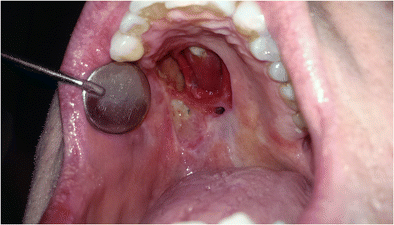

Necrosis is the death of body tissue. Fat necrosis is a condition that occurs when a person experiences an injury to an area of fatty tissue. 1  there are many types of necrosis, as it can affect many areas of the body, including bone, skin, organs and other tissues. Without a supply of blood, the affected bone and the tissue that surrounds it can gradually begin to die. Necrosis is a dramatic and very rapid form of cell death in which essentially every compartment of the cell disintegrates necrosis is characterized by marked dysregulation of ion homeostasis resulting in cell swelling, dilation of mitochondria and the er and the formation of vacuoles in the cytoplasm.

Necrosis is the pattern of cell death that occurs in response to injuries such as hypoxia, extremes of temperature, toxins, physical trauma, and infection with lytic viruses. Necrosis is the disorganized breakdown of flesh in some part of the body of a multicellular organism. Inflammation, reduction in aqueous humour production following ciliary epithelium necrosis, corneal opacity following necrosis of corneal epithelial cells, and visual loss and floaters following retinal necrosis). This can be from injury, radiation, or chemicals. Necrosis is the death of part of someone's body, for example because it is not getting. The dreaded condition known as gangrene, in which the dying tissue turns black or green, is another form. Cells need blood to live, and any interruption to blood flow results in. Necrosis is caused by a lack of blood and oxygen to the tissue. Avn can lead to joint pain, especially the hip. Necrosis is a dramatic and very rapid form of cell death in which essentially every compartment of the cell disintegrates necrosis is characterized by marked dysregulation of ion homeostasis resulting in cell swelling, dilation of mitochondria and the er and the formation of vacuoles in the cytoplasm. Causes of necrosis ischemia physical agents chemical agents immunological injury 4. Historically, the terms ischaemic and avascular necrosis were typically reserved for subchondral (epiphyseal) osteonecrosis, whereas bone infarct referred to medullary (metaphyseal) osteonecrosis. 1  there are many types of necrosis, as it can affect many areas of the body, including bone, skin, organs and other tissues.

When large areas of tissue die due to a lack of blood supply, the condition is called gangrene. Necrosis is the death of part of someone's body, for example because it is not getting. Necrosis synonyms, necrosis pronunciation, necrosis translation, english dictionary definition of necrosis. It is less orderly than apoptosis, which are part of programmed cell death. Cells die naturally after a period of time, but may also die as a result of injuries, infections, or cancer. It occurs when too little blood flows to the tissue. Necrosis is caused by a lack of blood and oxygen to the tissue. Necrosis is a general term that means a cell has died. It can affect any part of the body but typically starts in the toes, feet, fingers and hands. Death of cell tissues 2. The dreaded condition known as gangrene, in which the dying tissue turns black or green, is another form. Necrosis is the disorganized breakdown of flesh in some part of the body of a multicellular organism. Causes of necrosis ischemia physical agents chemical agents immunological injury 4.